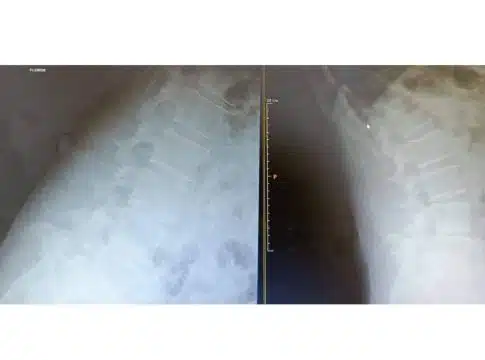

Su ejecución, por otra parte, se lleva a cabo en un quirófano bajo sedación y anestesia local, para lo cual es necesario hacer un estudio preparatorio con el anestesista en días previos. El procedimiento suele durar entre 30 y 50 minutos, durante los cuales, se realiza la extracción de los fragmentos del disco que provocan la dolencia. Para ello, se utiliza un fluoroscopio, que permite localizar con precisión la zona a intervenir y, así, evitar cualquier error o intervención en zonas que no se ven afectadas por la hernia.